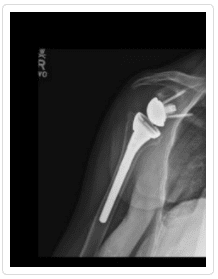

Total Shoulder Arthroplasty – A shoulder joint replacement surgery involves removing damaged bone and tissue and replacing them with artificial pieces or prosthesis. The procedure may involve only replacement of the head of the humerus bone or replacement of the entire ball and socket (glenoid) joint. The artificial components, made of metal or plastic, may be cemented into place or “press fit” into the socket if the bone is still in good condition.

Hemiarthroplasty – Also known as a partial replacement, a hemiarthroplasty involves replacing the humerus or arm bone with a prosthetic metal implant while the shoulder joint is left more or less intact. The shoulder osteoarthritis procedure may involve replacing the head of the humerus with a metal ball and stem as well as the arm bone or simply resurfacing the humerus head with a prosthesis that fits over the bone like a cap, preventing further wear and tear.